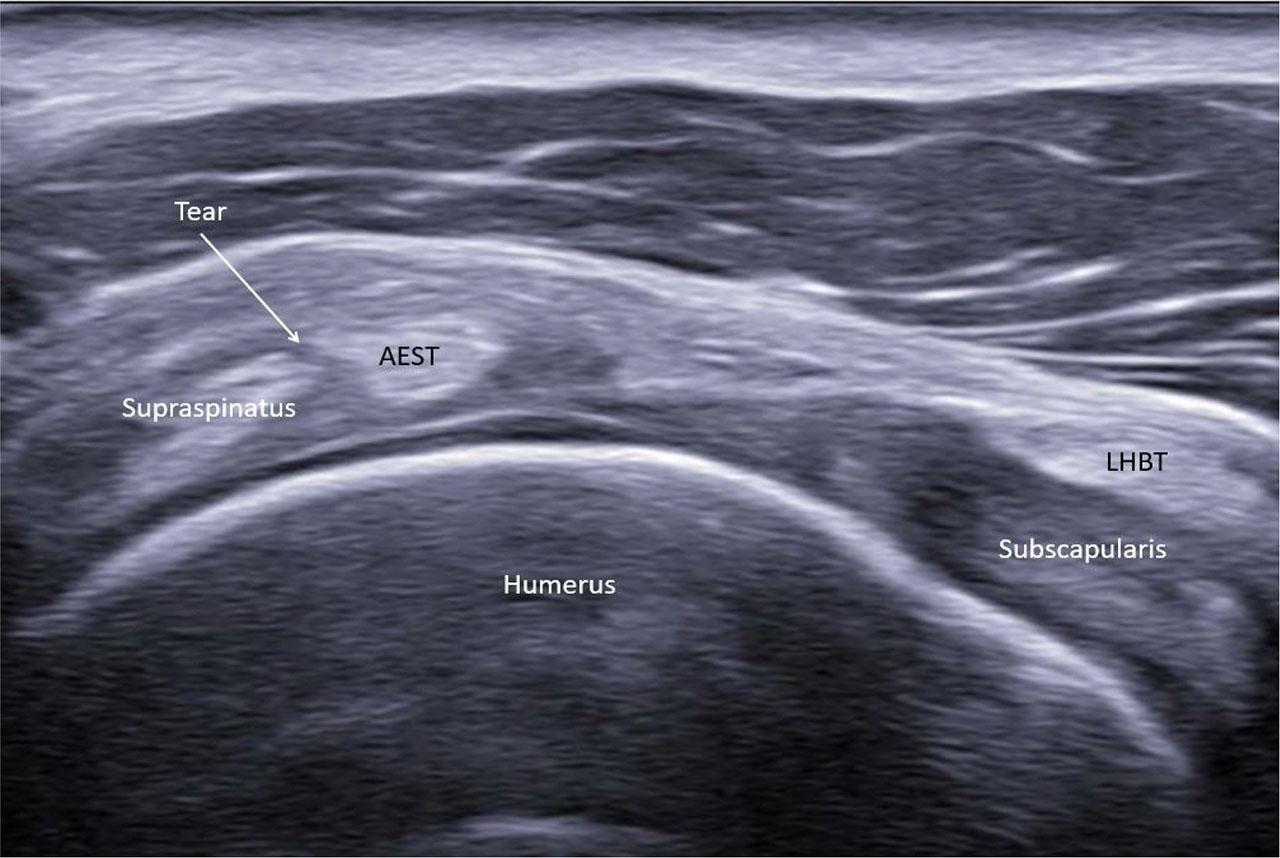

The most frequent abnormality was AEST dislocation with preserved intragroove LHBT, observed in six of 19 cases (31.6%) (Fig. 15). LHBT dislocation in the presence of intragroove AEST was identified in three cases (15.8%) (Fig. 16), while AEST intragroove subluxation with preserved LHBT alignment was found in another three cases (15.8%) (Fig. 17). Combined pathology included two cases (10.5%) of concomitant AEST and LHBT dislocation (Fig. 18), one case (5.3%) of LHBT subluxation with intragroove AEST, and one case (5.3%) of concomitant AEST and LHBT subluxation (Fig. 19). In four cases (21.1%), no abnormalities were observed.

Intragroove aponeurotic expansion of the supraspinatus tendon (AEST) with long head of the biceps tendon (LHBT) dislocation in the right shoulder (AEST–LHBT classification: IIIa, case 1)